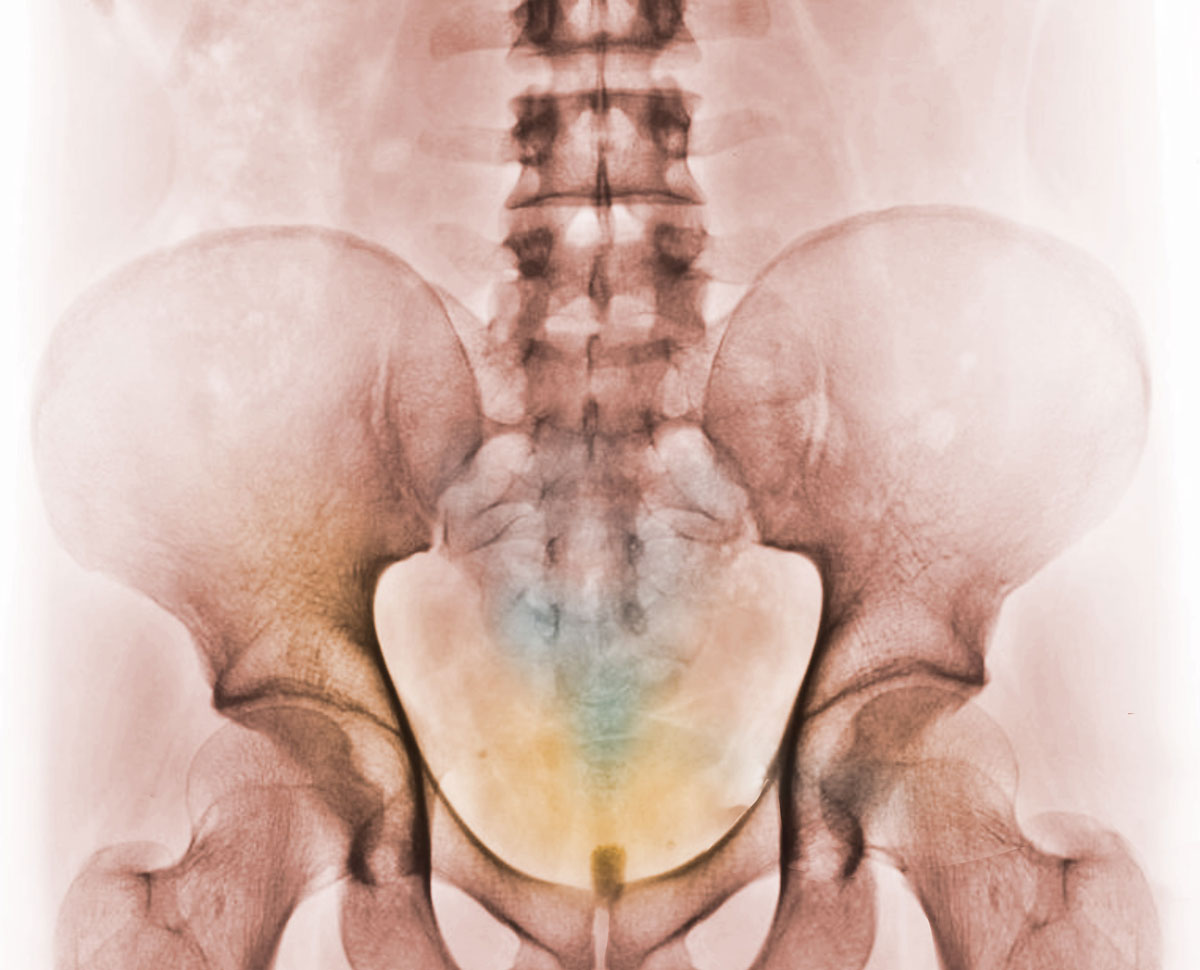

Openen van het skelet met de aarde als uitgangspunt

bekkenxraybasiscoloured1scaled